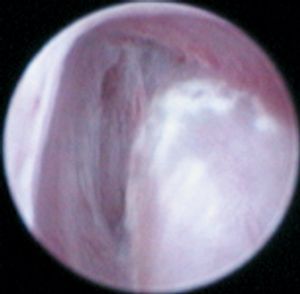

An 8-week-old 16.5-lb (7.5-kg) female Labrador retriever puppy was presented for evaluation of urinary incontinence. The puppy's incontinence had been present since the owner obtained the puppy at 4 weeks of age.